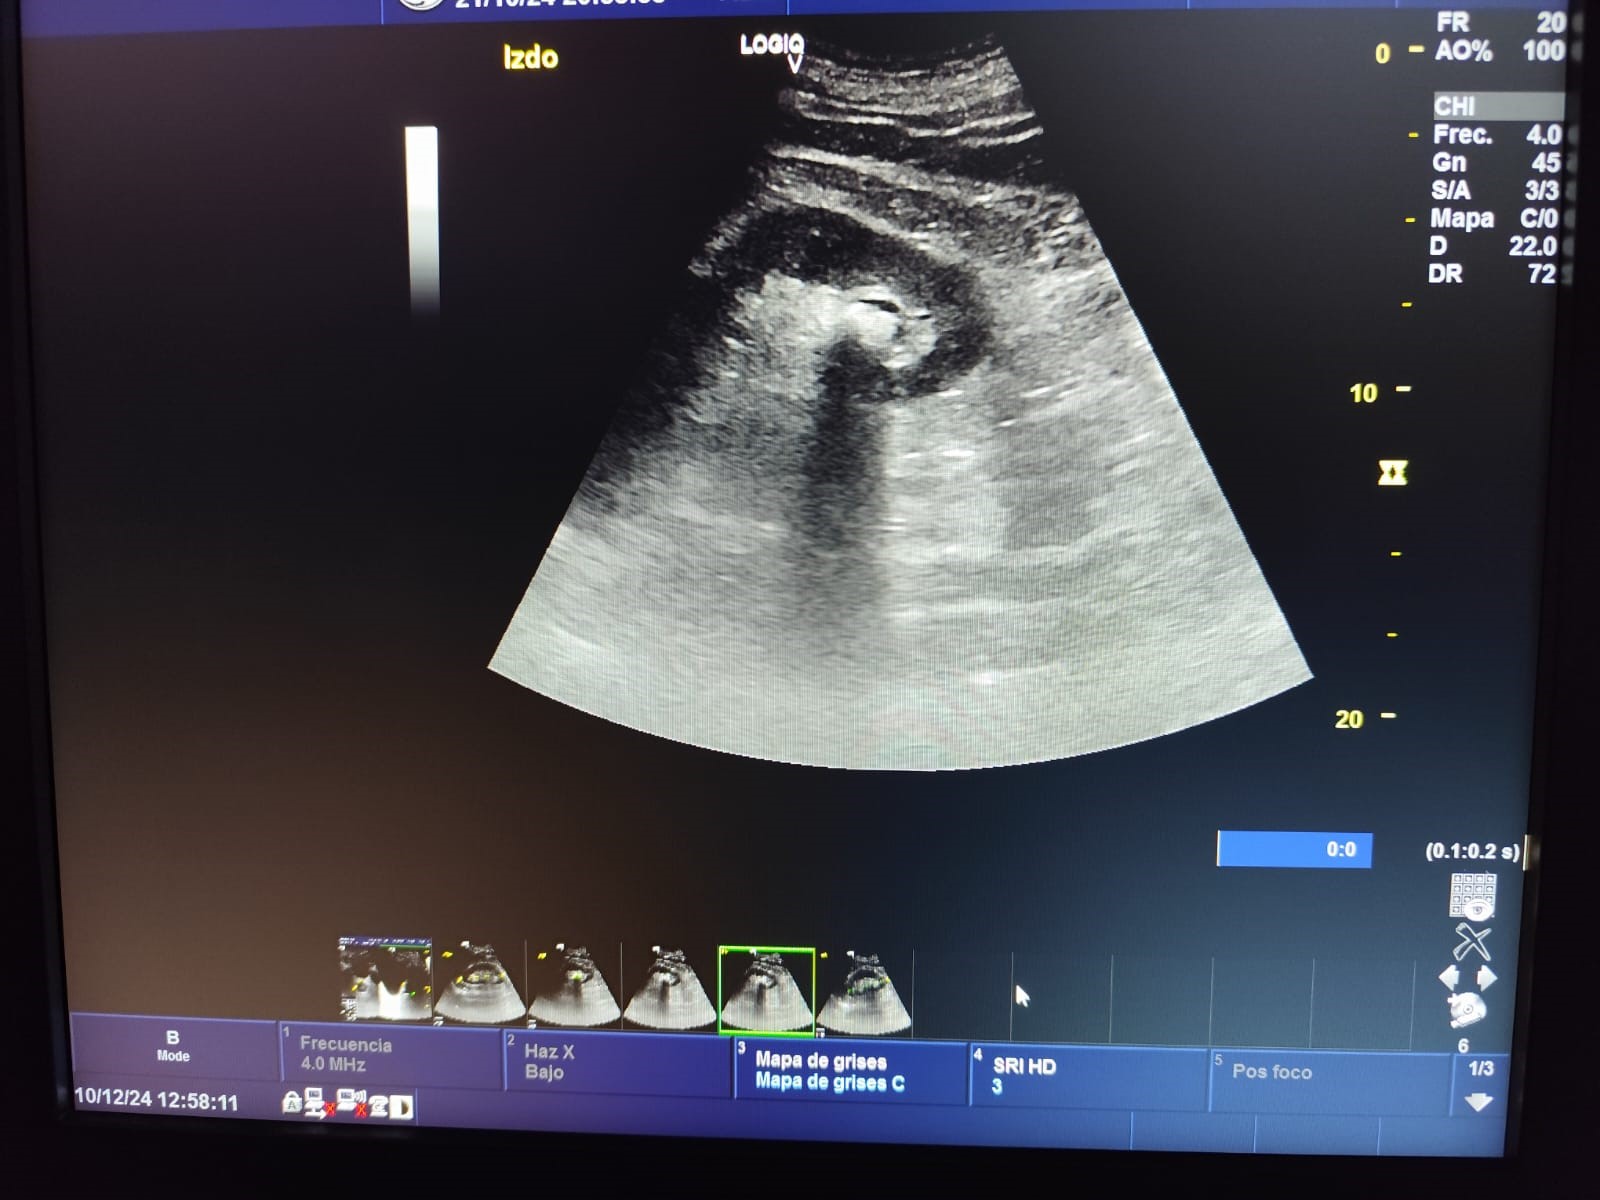

Descripción de los hallazgos ecográficos y las imágenes más relevantes para la resolución del caso

Ecografía en atención primaria (POCUS): Ecografía del riñón izquierdo: Litiasis de 1.4 cm en polo inferior, morfología y tamaño normales. Resto sin alteraciones.

Juicio clínico: Litiasis renal en riñón izquierdo, sin signos de hidronefrosis u otra complicación.

Realiza una nueva consulta por hematuria, sin aportar resultados de la prueba de imagen ya que se encuentra pendiente, por lo que se efectúa ecografía clínica en el Centro de Salud. El paciente realiza una videograbación del procedimiento ecográfico con el propósito de compartirla en la consulta de Urología, donde tras observar los resultados se remite a Litotricia Extracorpórea por Ondas de Choque.